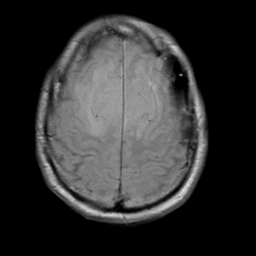

Meningioma, MR Study #2 -- Slice #16

[Home][Help][Clinical] Slice 16